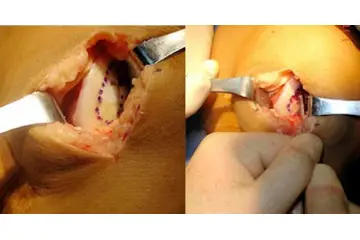

4. Tedavi Yöntemleri Diz kıkırdak aşınması tedavisi, hastanın durumuna ve aşınmanın derecesine bağlı olarak değişmektedir. Tedavi yöntemleri şunları içermektedir: